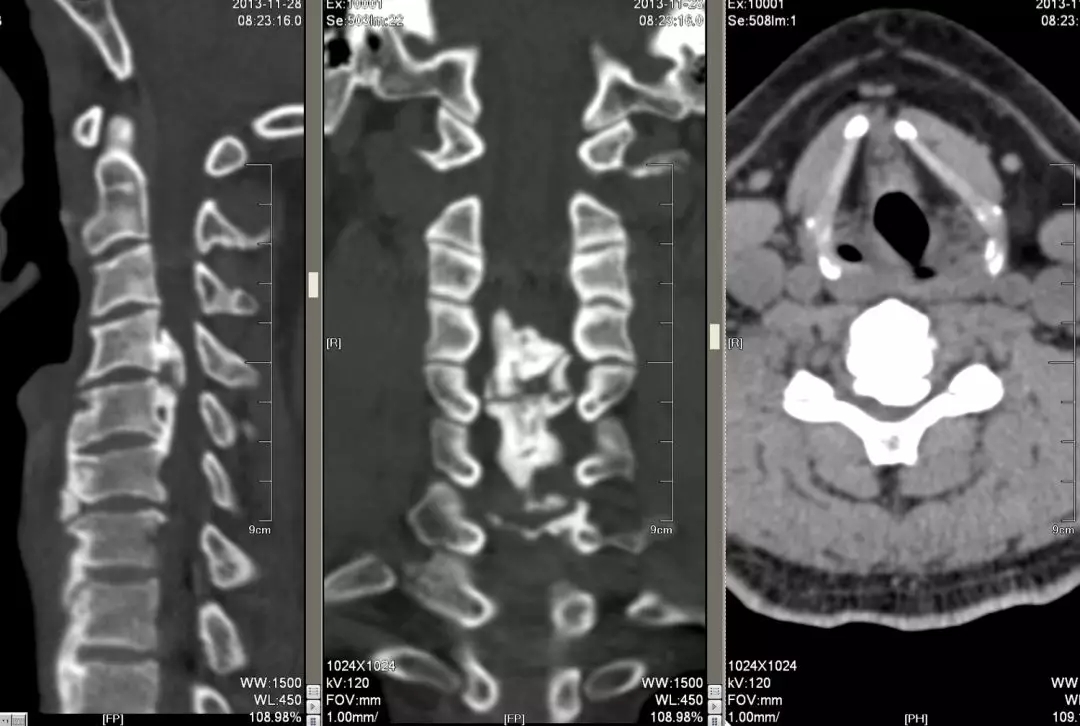

这是由于后纵韧带骨化,也造成了脊髓的受压,和脊髓型颈椎病有很多相似之处,但后纵韧带的骨化在ct相看的更加清楚,后纵韧带的骨化影像分型包括孤立型,间断型,连续型,混合型。它们对脊髓造成的损害,主要是通过挤压,折顶和挫磨引起的。在治疗方面,如果是四个椎节以内的孤立型,间断型可以选择前路手术进行致压物的切除和椎间融合。如果是四个椎节以上的连续型,混合型则选择后路椎管切除,椎管成形术。

这是同一个病的ct,我们可以看到很明显的后纵韧带的骨化,